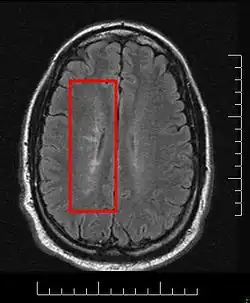

Dawson's Fingers appearing on an MRI scan |

This morphologic appearance was named Dawson's fingers by Charles Lumsden, after the Scottish pathologist James Walker Dawson,[31] who first defined the condition in 1916.

Dawson's fingers

"Dawson's fingers" is the name for the lesions around the ventricle-based brain veins[32][33] of patients with multiple sclerosis and antiMOG associated encephalomyelitis[34]

Though once thought to be specific of MS, it is known not to be the case.[35]

The condition is thought to be the result of inflammation or mechanical damage by blood pressure[30] around long axis of medular veins.

Dawson's fingers spread along, and from, large periventricular collecting veins, and are attributed to perivenular inflammation.[36]

Lesions far away from these veins are known as Steiner's splashes.[30]